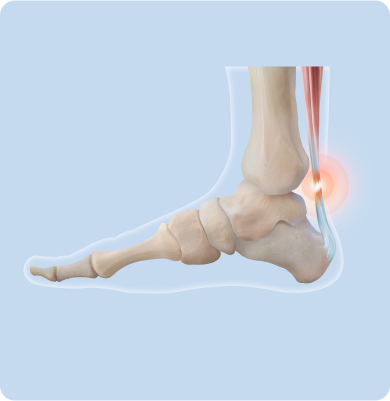

종아리 근육과 발꿈치를 연결하는 아킬레스건에 염증이 생기는 질환

갑작스러운 운동량 증가, 준비 운동 없이 무리한 활동, 딱딱한 바닥에서의 반복적 충격, 하이힐이나 맞지 않는 신발 착용, 종아리 근육의 유연성 저하 등이 아킬레스건에 반복적인 자극을 주어 발생합니다.